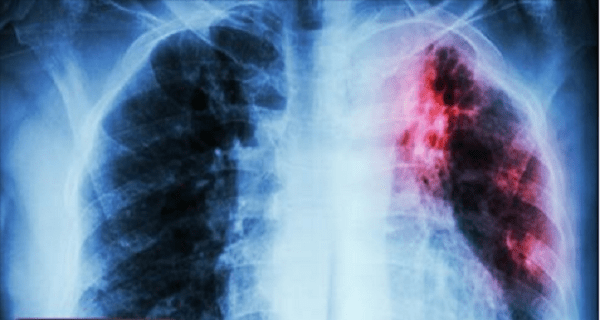

Smoking is one of the most detrimental habits you can have, as it severely damages health and leads to various ailments. More than 16 million Americans suffer from some health problems as a result of smoking, and for every individual killed by this deadly habit, at least 30 people live with a severe smoking related […]